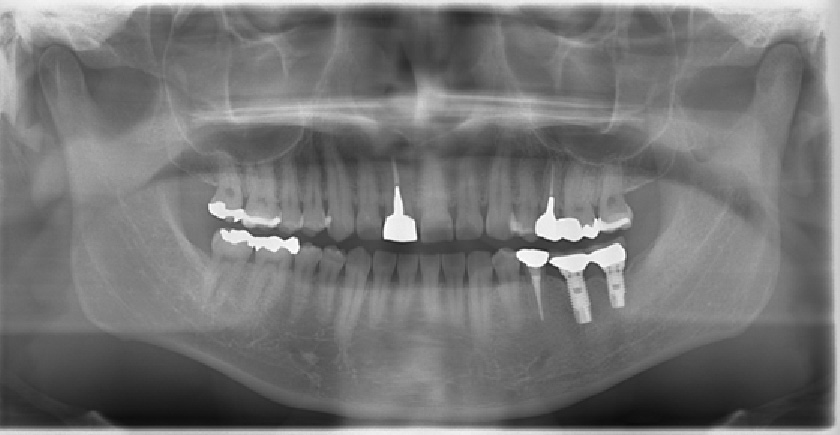

• 術前術後のレントゲン写真

写真向かって、右下の奥歯が割れてしまっているので、抜歯し、そこに人工歯根として、インプラントを埋め込んだレントゲン写真です。